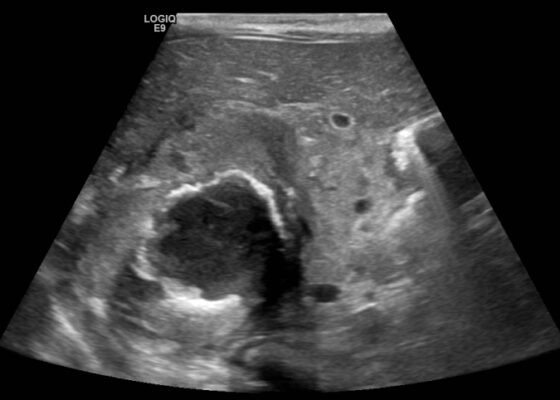

DOI: https://doi.org/10.21980/J8SQ0ZThe ultrasound images reveal hepatomegaly and an increased echogenicity of the liver parenchyma that is diffuse. The increased echogenicity can be best appreciated by a comparison to surrounding structures. It is important to note that the increased echogenicity is non-focal and consistent throughout the entire liver in multiple views. These findings can be consistent with nonalcoholic steatohepatitis as well as glycogenic hepatopathy.

DOI: https://doi.org/10.21980/J8QQ0BAn ultrasound (US) of the abdomen was obtained to evaluate for possible pyloric stenosis (see US transverse/dopper imaging). While imaging showed a normal pyloric channel, it revealed an unexpected finding: a complex cystic mass arising from the right adrenal gland (yellow outline), measuring 5.8 by 4.0 by 6.4 cm with calcifications peripherally and mass effect on the kidney without evidence of vascular flow (blue arrow). Computed tomography (CT) of the abdomen/pelvis with IV contrast was subsequently obtained and measured the lesion as 2.8 by 4.6 by 4 cm without evidence of additional masses, lymphadenopathy or left adrenal gland abnormality (see CT axial, coronal, and sagittal imaging).